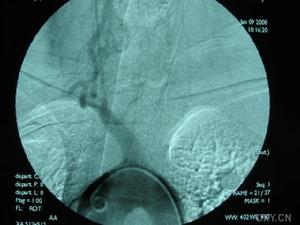

3.腦血管造影有一定的診斷價值71%以上的患者有典型的血管多灶性損害的表現,血管粗細不均,可呈節段性的狹窄或擴張血管阻塞及血管排空延遲等似“臘腸”樣改變,提示腦部血管炎的存在但不能明確是本病的血管炎其他的腦部繼發性血管炎也可有類似的表現有些可因受累的血管太小,腦血管造影可正常